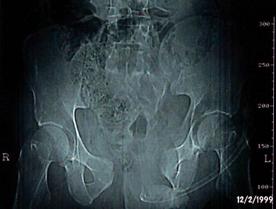

TRAUMATISMELE PELVIENE

Traumatism

pelvian Hemipelviectomie dreapta posttraumatica

Banda de stabilizare Dallas Fractura de bazin. Radiografie in

incidenta AP

Fractura de bazin

. Radiografie in incidenta AP Fractura de spina